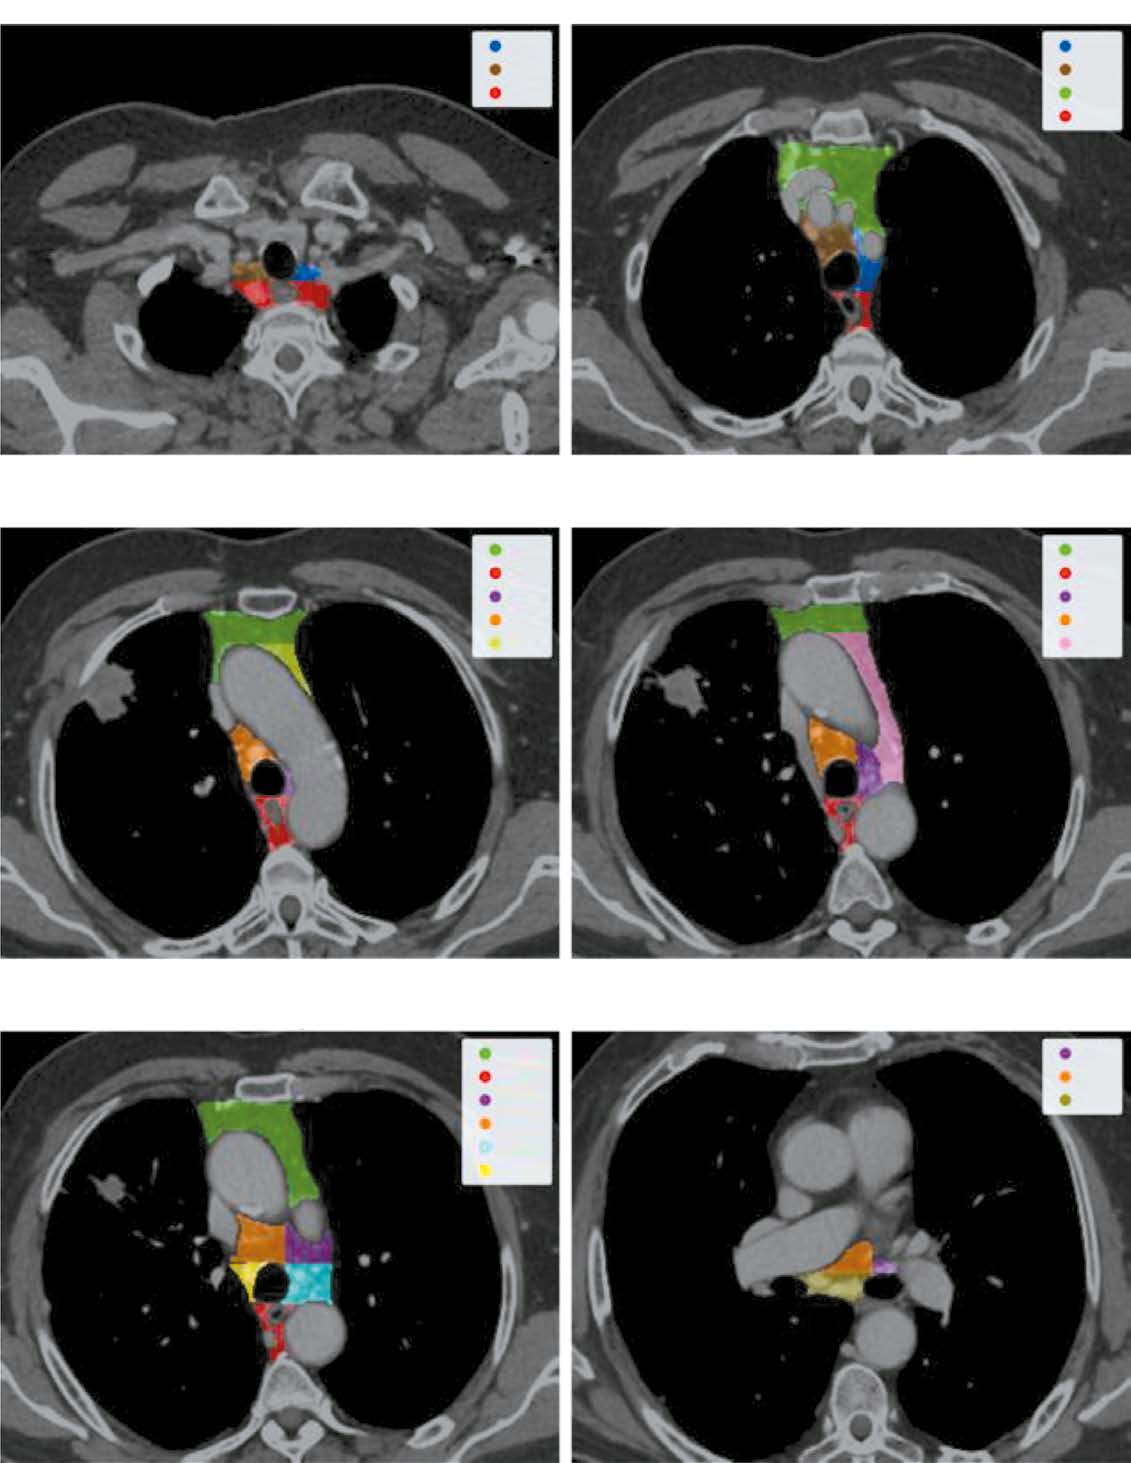

BACKGROUND: Lung cancer is the second most common cancer worldwide, accounting for approximately 20% of all cancer related deaths and having a <10% 5 year survival rate for very late stage cases. For the prevalent non small cell lung cancer (NSCLC), recent guidelines advise staging based on the 8th edition of the TNM classification, highlighting the importance of mediastinal lymph node involvement. While noninvasive methods are generally accurate, they often lack sensitivity, and invasive methods may not be suitable for all patients. Advances in deep learning present potential in solving such problems. However, most research focuses on algorithm development more than clinical relevance. Moreover, none of them addressed individual lymph node malignancies, limiting comprehensive analysis and interpretability and leaving clinicians without sufficient means to validate the results effectively.

AIM: To develop a local data trained and validated algorithm for segmenting each mediastinal lymph node in chest computed tomography (CT) and assessing the probability of its involvement in metastasis.

MATERIALS AND METHODS: Initially, IASLC lymph node stations are segmented, providing a bounding box of the mediastinum for further processing. Next, the image is cropped to this box and passed through a second network to identify and mask all visible lymph nodes. Finally, each detected lymph node is extracted, stacked with its mask, and evaluated by a feed-forward network to determine malignancy probabilities.

RESULTS: The pipeline achieved an average recall and object Dice Score of 0.74±0.01 and 0.53±0.26 for the clinically relevant lymph node segmentation task. Further, it recorded a 0.73 ROC AUC for predicting a patient’s N-stage, outperforming traditional size based criteria.

CONCLUSIONS: The proposed algorithm enables new research algorithms to optimize the management of patients with nonenlarged intrathoracic lymph nodes, thus improving the quality of medical care for patients with cancer.